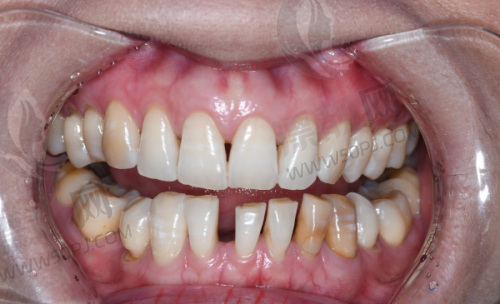

强项:高难度种植、全口修复、吸附性义齿

鼎植口腔在本地做种植牙的人中几乎是“必打卡单位”,医生高振华和黎强在种植牙领域经验颇为丰富,擅长全口吸附性义齿、即刻种植等复杂病例处理。此外,术前会有CBCT影像分析和3D导板定位,精细度特别高。价格一般,活动期间国产种植体可低至2980元/颗。